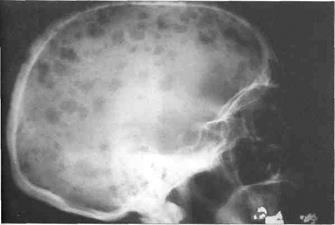

Рентгенография позвоночника – остеопороз, снижение высоты дисков L1-L 2